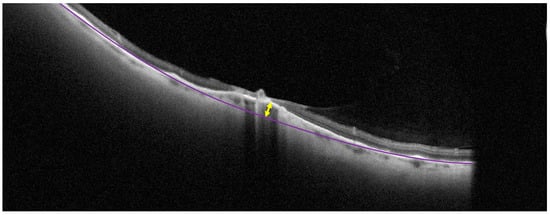

Figure 1. Measurement of choroidal indentation on a cross-sectional optical coherence tomography scan. The purple line represents the level of retinal pigment epithelium. The yellow arrow shows the maximum scleral indentation in the middle of the lesion.